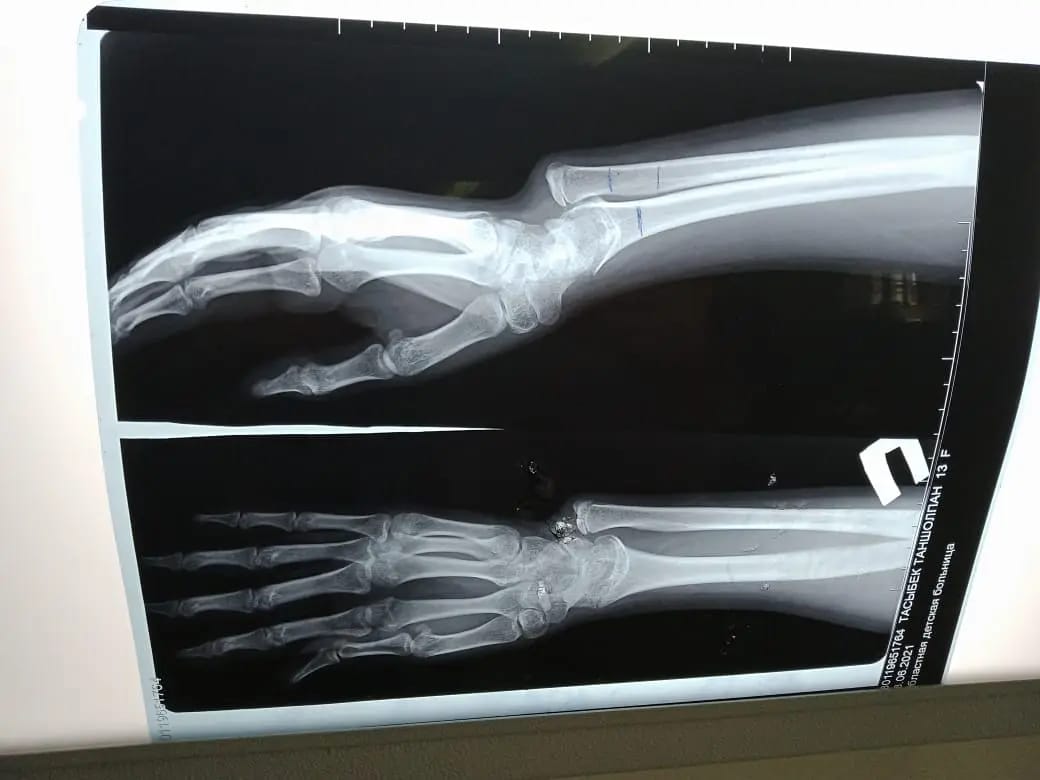

Науқас осыдан бірнеше жыл бұрын қолын ауыр жарақаттап, шынтақ сүйегі өсіп, кәрі (лучевая) сүйегі өспей қалған. Салдарынан қолындағы сүйектері қисайып, өздігінен қимыл жасауға кедергі келтірген.

«Ота жасалған науқас үш ай бұрын қалалық клиникалық балалар ауруханасына кеңес алуға келген болатын. Тексере келе науқаста жарақаттың салдарынан сүйегі қисайғаны анықталды. Операцияны бірден жасамадық. Себебі мұндай ота баланың сүйек өсуі тоқтауға жақындаған кезде жасалады. Операция кезінде қатты өсіп кеткен сүйекті қысқартып, өспей қалған сүйекке жалғап, арнайы құрылғымен бекітіп бердік. Мұндай отаны бірінші рет жасадық. Осыған дейін сүйегі қисық өскен науқастарға ота жасау үшін Нұр-Сұлтан қаласындағы емдеу мекемелеріне жолдама арқылы жіберетінбіз. Енді міне мұндай отаны өзіміз жасауға дайынбыз» дейді ортопед-травматолог Бағжан Тұрдықұлов.